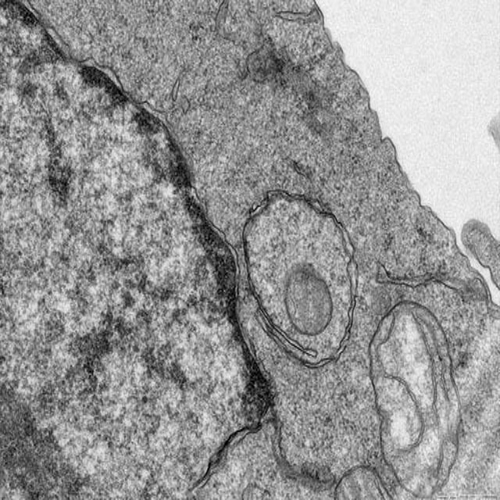

透射电子显微镜(Transmission Electron Microscopy, TEM)是研究生物组织超微结构的金标准技术,可提供亚细胞器水平(0.1-0.5 nm分辨率)的高对比度成像。本中心提供专业级生物组织TEM全流程技术服务,涵盖样品制备、超薄切片、染色观察到图像分析的全链条解决方案。

原子级分辨率:0.34nm晶格分辨率,清晰显示核孔、核糖体等超微结构

细胞生物学:线粒体嵴形态、内质网结构、自噬体观察

神经科学:突触小泡计数、髓鞘板层分析

病理诊断:病毒颗粒鉴定、纤维化胶原排列研究